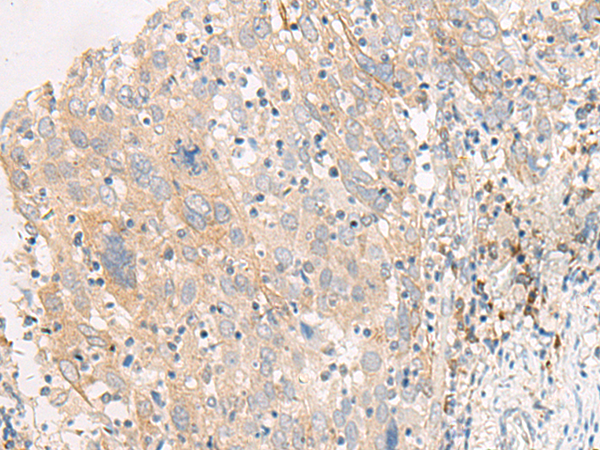

IHC positive control: |

Human cervical cancer |

IHC Recommend dilution: |

25-100 |